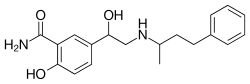

| Labetalol | Trandate |

|

Blocks some α1 receptor activity, but binds more strongly to β receptors.[2] | Lowers blood pressure, increases heart rate slightly.[2] |

| |